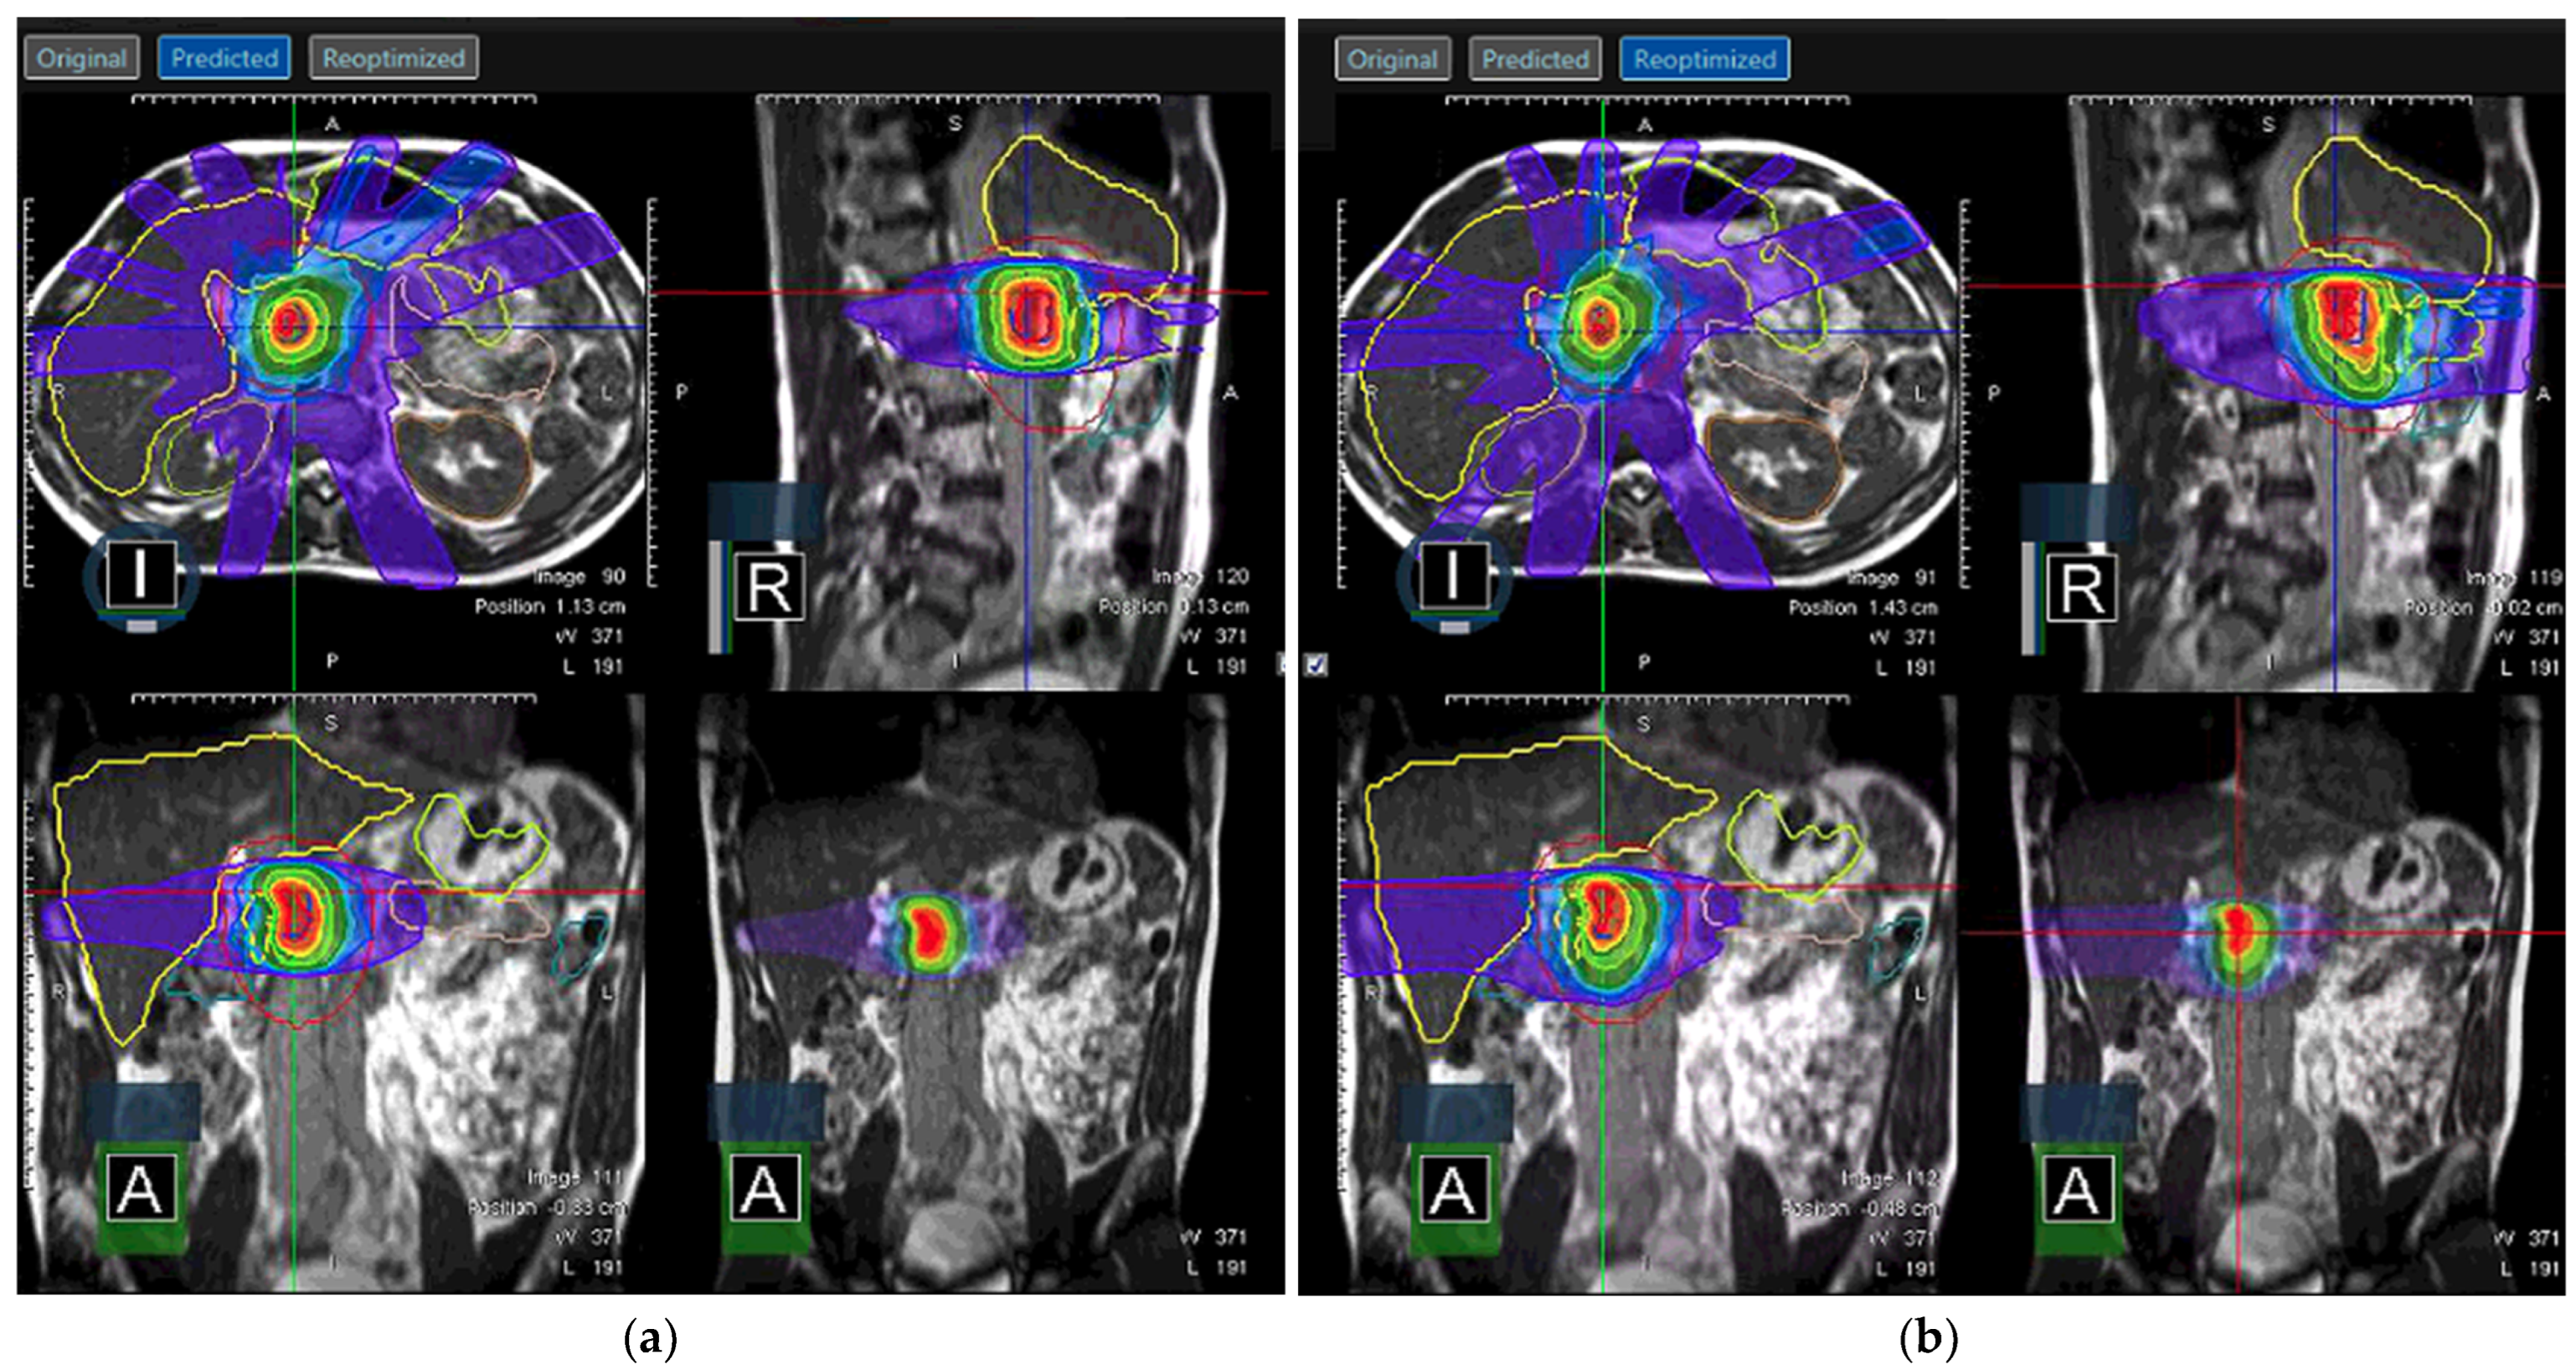

Soft tissue delineation is greatly improved in MRI when compared to CT and can help avoid OARs that would otherwise be crowded by organs of similar electron density on CT. Improved visualization of targets and organs at risk is then combined with the potential for treatment adaptation based on real-time imaging. Altering the initial radiotherapy plan to better fit patient anatomy is especially critical in a body with moving structures, such as those of the abdomen, where toxicity is a significant risk and organs lie in close adjacency (see Figure 6). Multiple studies have shown dosimetric benefit of increased target coverage and reduced dose to normal structures by utilization of adaptative radiotherapy afforded by MRgRT [73,74] with translation to good clinical outcomes [75,76].

Figure 6.

Adapted radiotherapy plan on ViewRay MRIdian for abdominal target. (a) The predicted plan was found to have inadequate target coverage and/or OAR sparing (blue color) and (b) was adapted to produce the reoptimized plan. Note the change in dose to stomach on the axial slice.